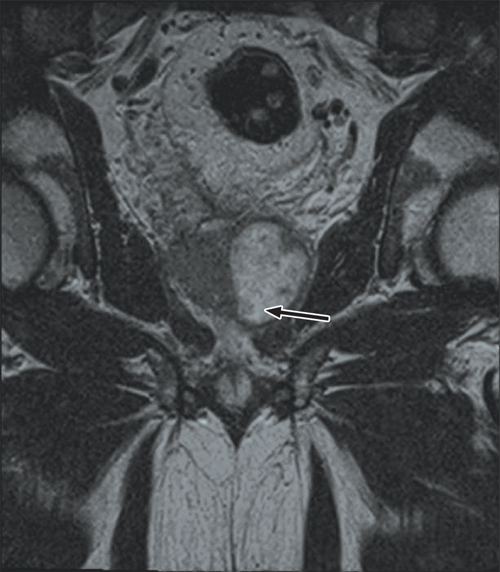

Despite ongoing cephazolin therapy, the patient developed increasing pain over the right sternoclavicular joint. Computed tomography imaging demonstrated changes consistent with a joint effusion, localised oedema, septic arthritis and osteomyelitis of the upper manubrium and medial right clavicle (Box 2). After initial conservative management without symptom resolution, surgical debridement was performed, and culture of the excised tissue grew MDR E. coli. The patient subsequently complained of lumbar back pain, and MRI of the lumbar spine showed changes consistent with an epidural abscess together with immediately adjacent discitis and osteomyelitis at the L4–5 vertebrae (Box 3). An orthopaedic consultation recommended conservative management, and the patient’s primary care was transferred to infectious diseases physicians. After 5 weeks of intravenous cephazolin therapy in hospital, he was discharged with a treatment regimen of intravenous ceftriaxone 2 g daily delivered by an elastomeric infusion device (Baxter) managed by the home-based acute care service.

The patient was readmitted the day after discharge with increasing abdominal pain and continuing back pain. Repeat MRI of the lumbar spine showed slight radiological progression. The ceftriaxone dose was increased to 2 g twice daily, with ongoing conservative management of the spinal osteomyelitis. At the end of this second long-term admission (47 days), the patient had made significant clinical improvement and was discharged for ongoing outpatient-based rehabilitation, with a regimen of oral fosfomycin 3 g daily. In total, he received 10 weeks of intravenous antibiotics and 8 weeks of oral fosfomycin.